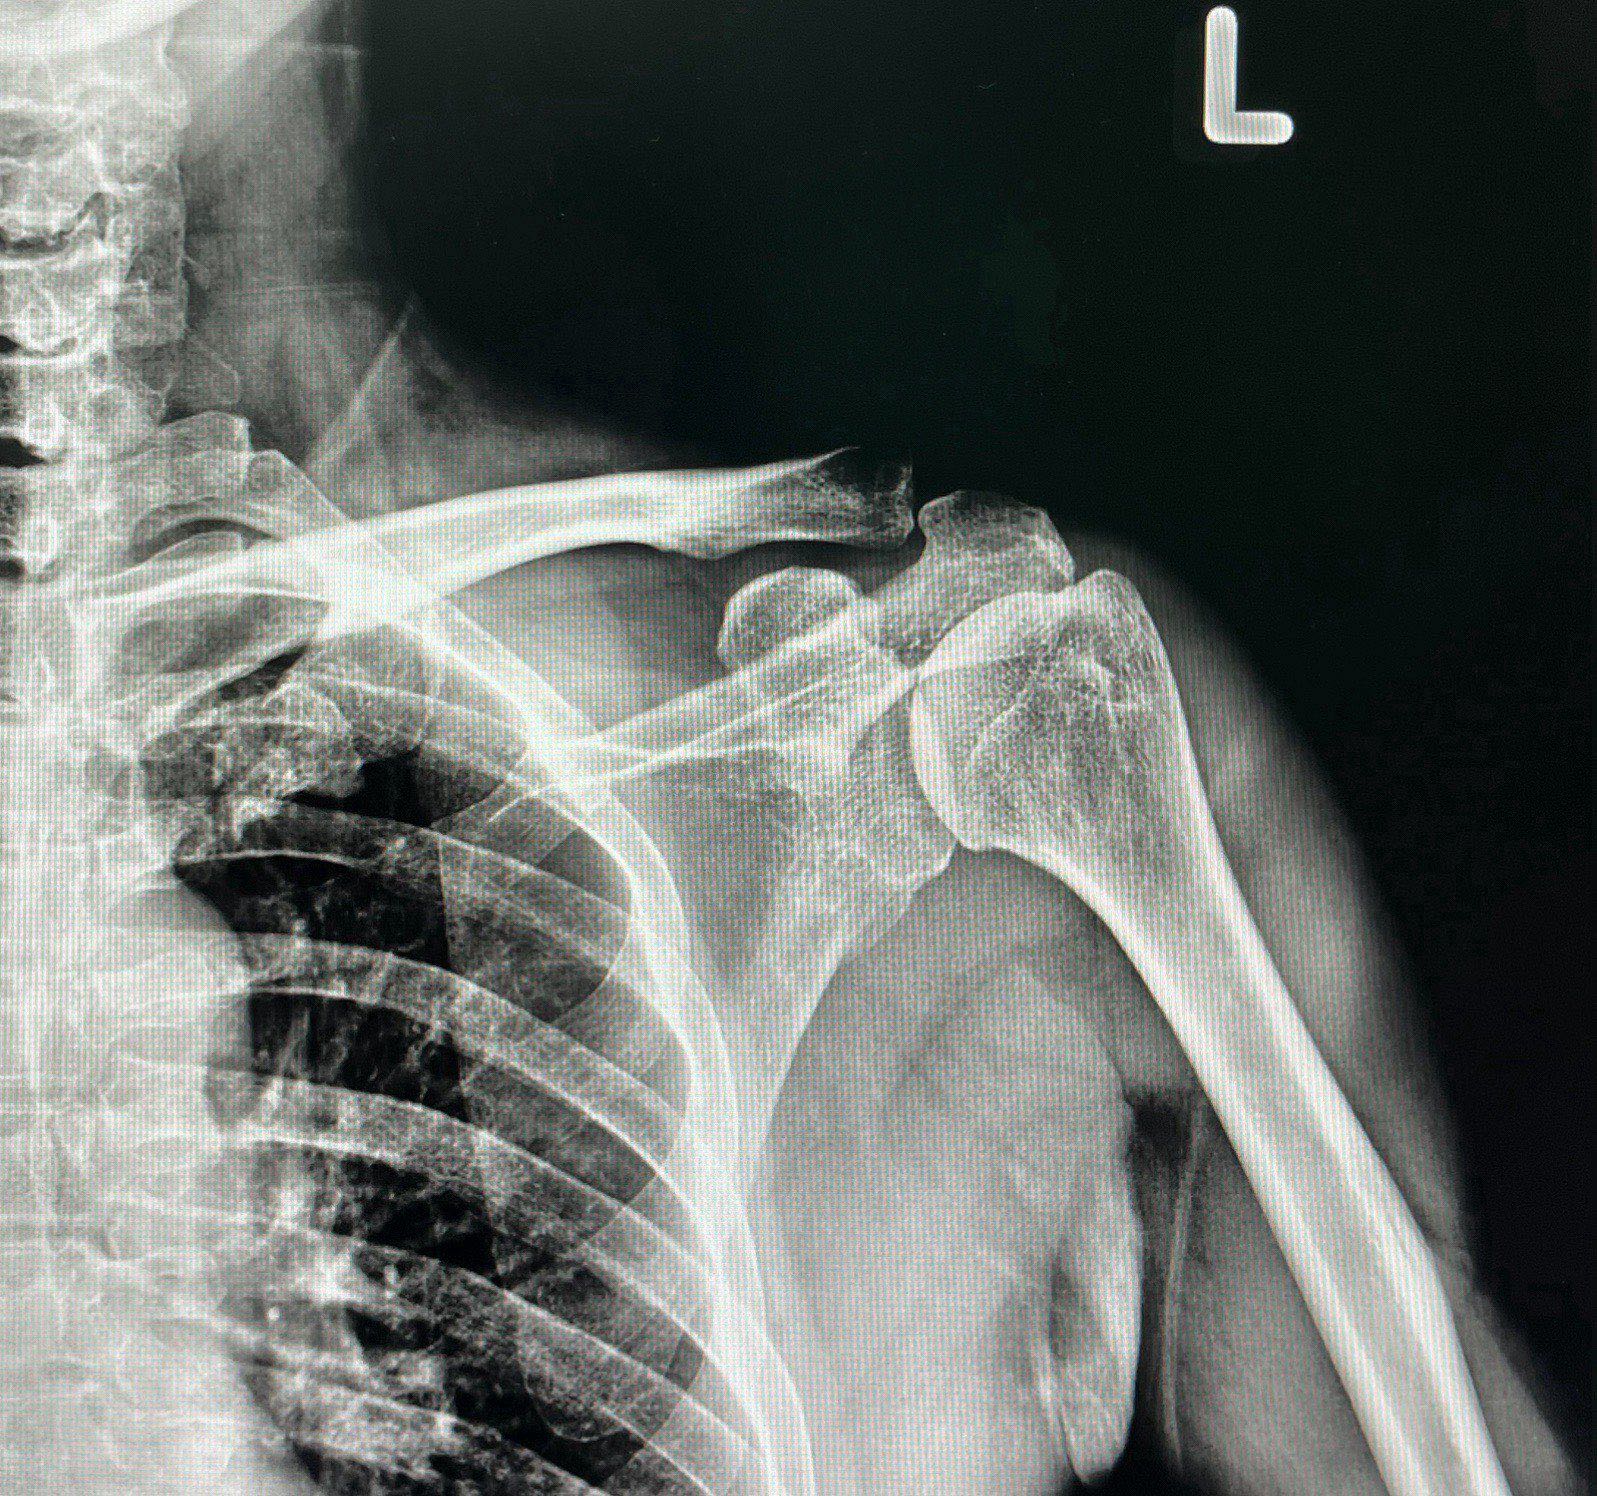

หากคุณรู้สึกปวดไหล่จนถึงขั้นทำกิจวัตรประจำวันลำบาก เช่น การยกแขน นอนหลับ หรือทำงาน และอาการไม่ดีขึ้นแม้พักผ่อนหรือใช้ยาบรรเทาปวด อาจเป็นสัญญาณของ การบาดเจ็บรุนแรง เช่น เอ็นไหล่ฉีกขาด หรือการอักเสบเรื้อรัง ที่ควรได้รับการตรวจวินิจฉัยอย่างละเอียด

7. มีประวัติการบาดเจ็บที่ไหล่หรือเคยผ่าตัดไหล่มาก่อน

ถ้าคุณเคยมีประวัติการบาดเจ็บที่ไหล่ เช่น ไหล่หลุด ไหล่ฉีกขาด หรือเคยผ่าตัดไหล่มาก่อน และรู้สึกปวดหรือมีปัญหาในการใช้งานไหล่อีกครั้ง ควรรีบพบแพทย์เพื่อป้องกันการเกิดซ้ำหรือภาวะแทรกซ้อน